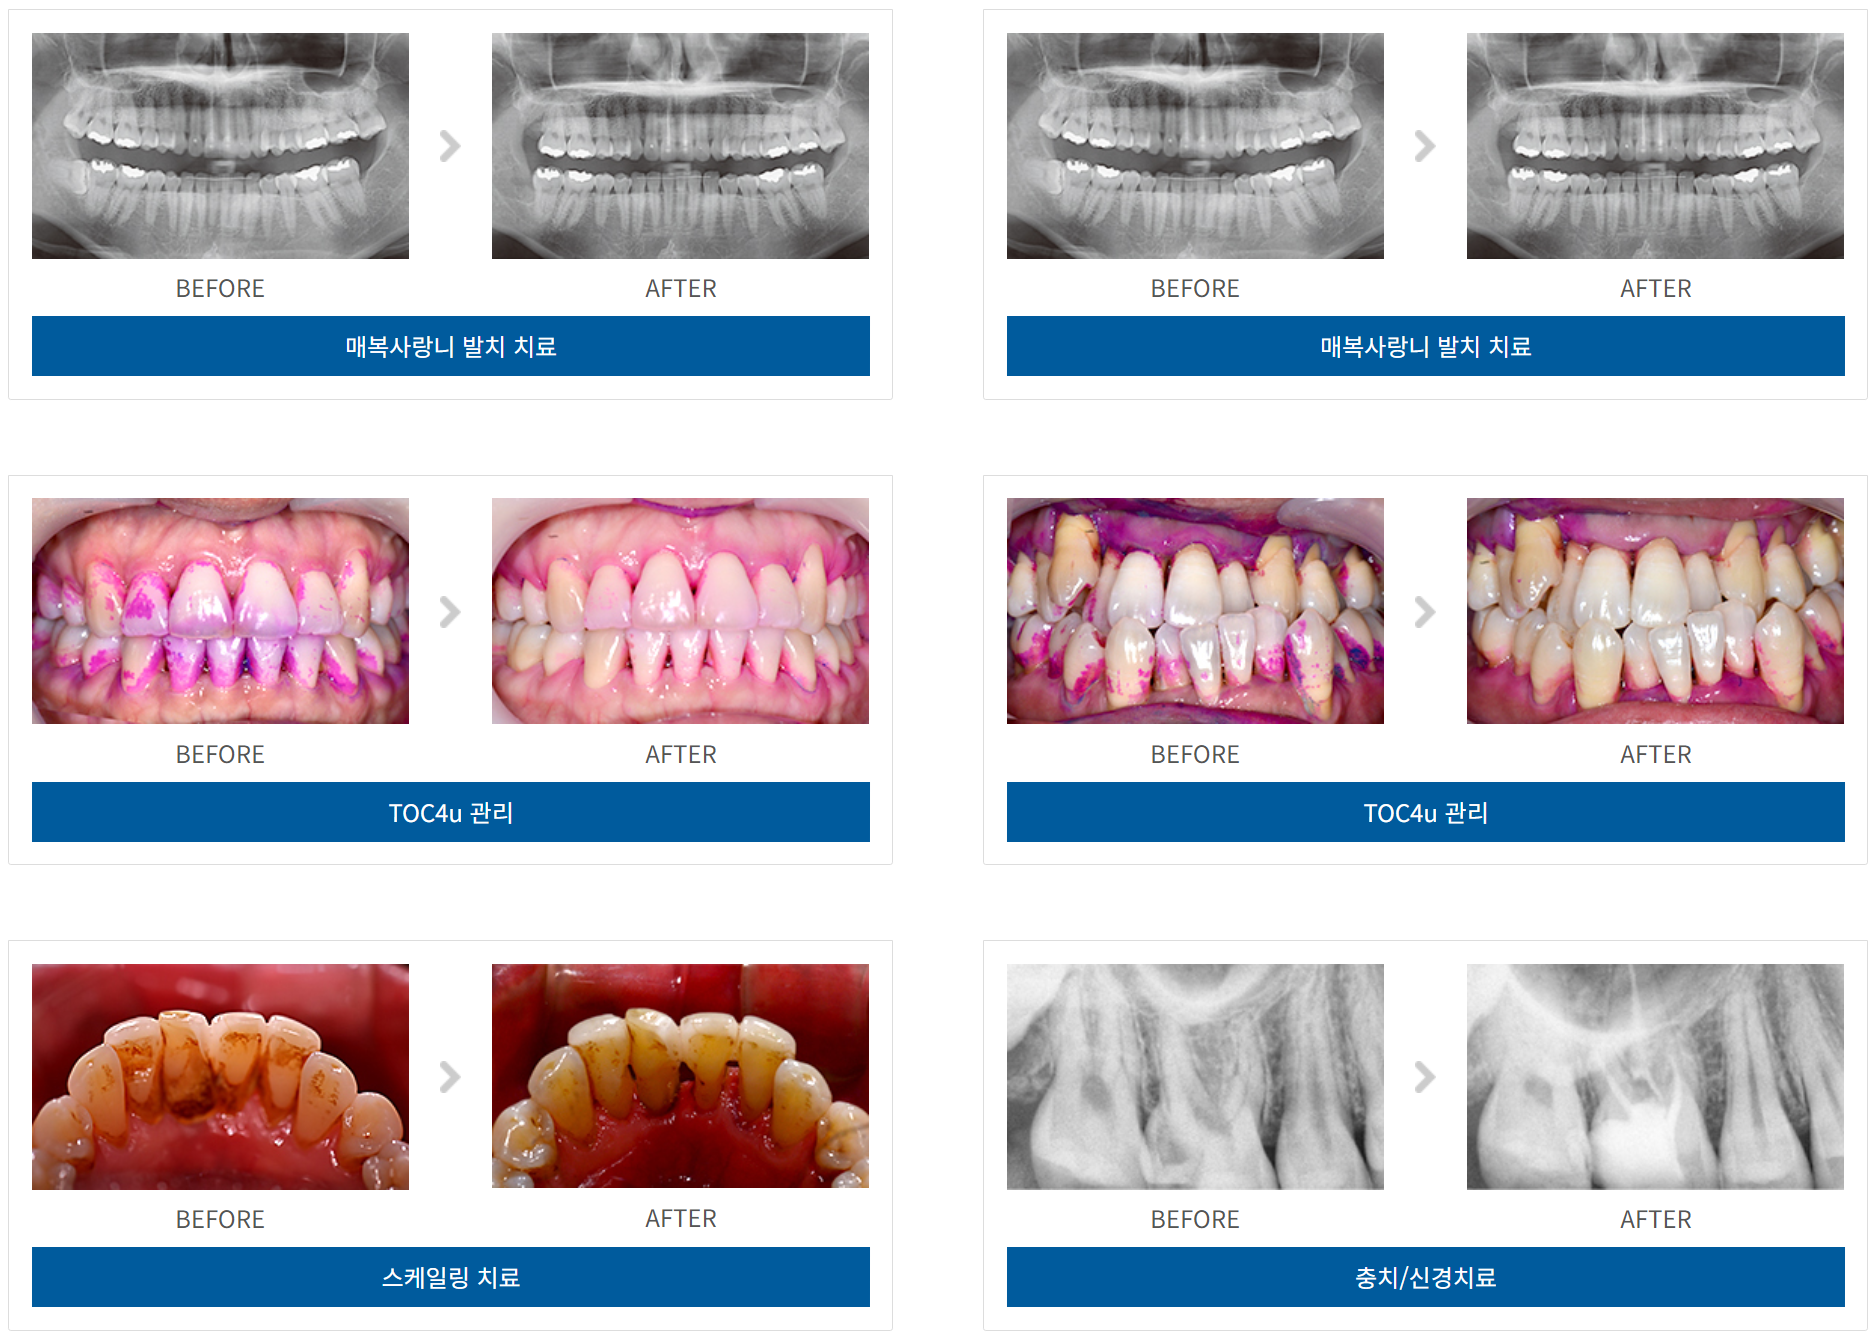

일반치료 케이스